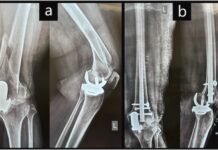

Said Dr. Rajani, “We are seeing several long-term trends in India that signal a growing orthopaedic burden. Due to earlier onset of degenerative conditions, especially in knees and shoulders, there is increasing demand for joint preservation procedures like arthroscopy, PRP, and stem cell injections, especially among the 30–50 age group. A higher number of joint replacements are today being performed in younger patients.”